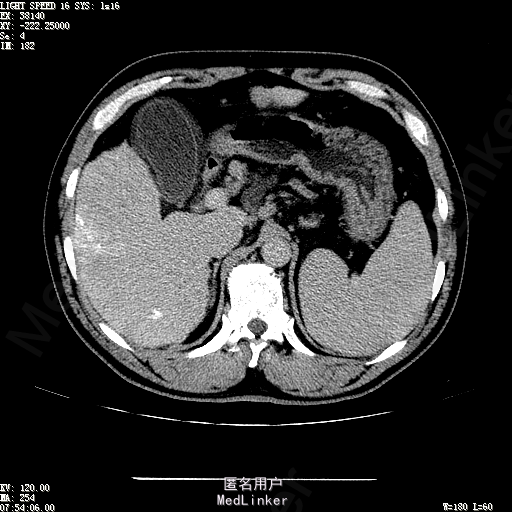

主诉:肝癌TACE治疗后36天 病史:患者两年前体检发现丙型肝炎病毒标志物阳性,于当地医院就诊诊断为"丙肝肝硬化",口服药物治疗,具体用药不详。定期复查肝功及肝脏影像学检查,2月前于医大二院行肝脏增强磁共振检查发现肝S6段动脉期增强结节,36天前在我院行DSA肝动脉造影明确"原发性肝癌"诊断并行"TACE"治疗,术后恢复良好,现患者为进一步行肝癌局部消融治疗来诊。

诊断:1、丙肝肝硬化 代偿期;2、原发性肝癌 S5段、S6段 该患诊断明确,既往曾行TACE治疗肝癌,S5段、S6段近右肾上极2处碘油沉积明确,S5段者较大,约2.31cm。超声显示清晰,为防止癌灶复发,适合行射频消融治疗。